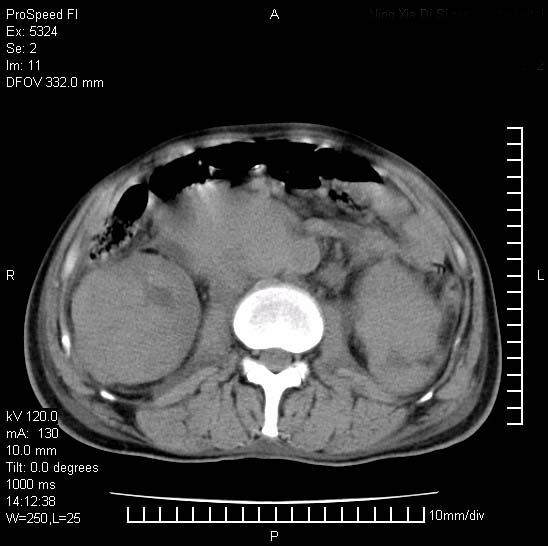

患者阴囊肿大14月,腰痛2个月,咳嗽,咳痰1周,患者现在肾功异常,做增强有些担心,我们用的是欧乃派克.

双肾均有软组织密度舯物,腹膜后淋巴结肿大包饶腔静脉------考虑为恶性占位病变,转移瘤可能。

腹腔积液,双肾均有稍高密度肿块,主动脉旁广泛淋巴结肿大,融合,无显著肿块坏死征像,多考虑淋巴瘤累及双肾,不排除肾癌伴转移(肾癌这么大应该较多坏死了),另阴囊肿大,不知是实质肿大还是阴囊积液,如是是积液,多为腹腔肿块压近睾丸静脉所致,如是是实性的,多为淋巴瘤

双肾周围及腹膜后改变符合恶性病变,现在关键是要明确阴囊肿大的原因,是否为肿瘤性病变.如阴囊为恶性肿瘤那一切用转移即可解释,如阴囊为水肿改变,那需重新分析检查明确.

阴囊肿大是实质性的么,为什么不扫阴囊,此扫描做的是什么部位,肾脏没包括全,也可以考虑生殖系统肿瘤转移

双肾增大,腹膜后多发肿大淋巴结影.首先考虑淋巴瘤.

双肾增大,结合腹膜后淋巴结肿大,考虑双肾恶性肿瘤并转移可能。